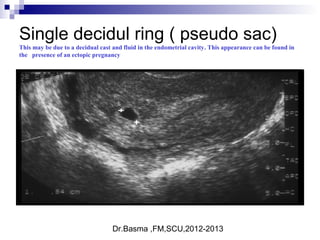

Single decidul ring ( pseudo sac)

This may be due to a decidual cast and fluid in the endometrial cavity. This appearance can be found in

the presence of an ectopic pregnancy